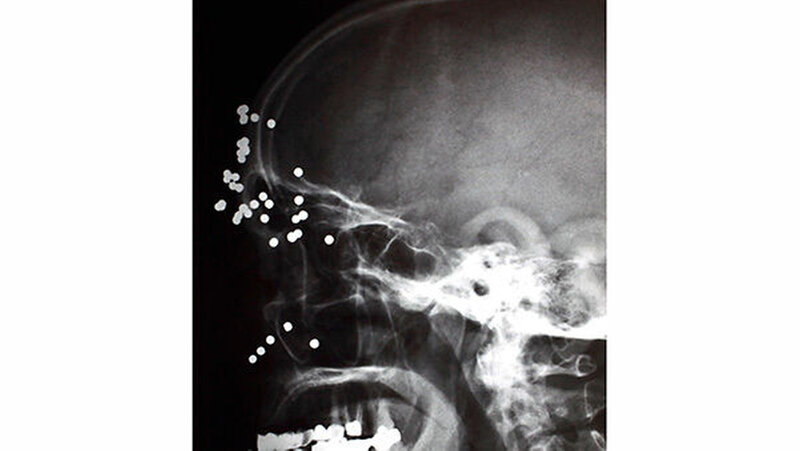

Vom Bohrer im Kopf bis zum Schlüssel in der Kieferhöhle: Die MKG-Chirurgen der Charité haben ausgewählte Patientenfälle mit Fremdkörpern im Gesicht zusammengestellt. In unserer Fotostrecke finden Sie die eindrucksvollen Aufnahmen.